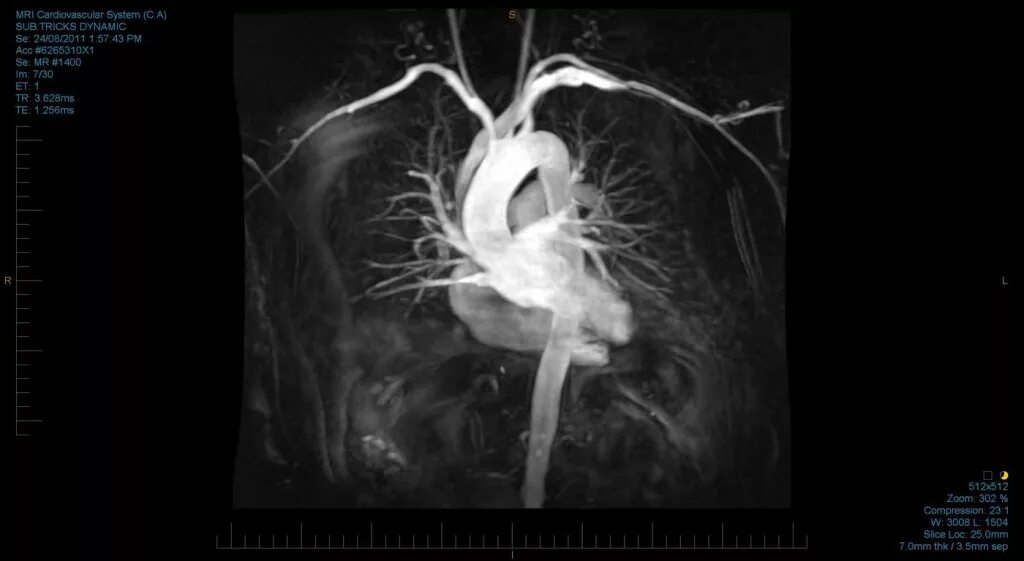

Как делают кт сердца